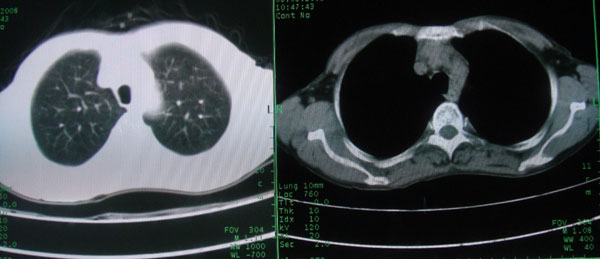

标题: CT15046:F59Y,咳嗽间断咳血丝痰就诊. [打印本页]

标题: CT15046:F59Y,咳嗽间断咳血丝痰就诊.

咳嗽\间断咳血丝痰就诊.